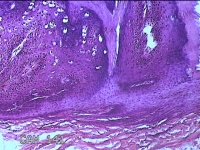

右侧拇指皮下结节

性别

男

年龄

40岁

临床诊断

皮下结节

一般病史

发现右侧拇指皮下结节1年余,无明显疼痛及不适。

标本名称

大体所见

灰白暗红色带皮肤结节0.8x0.3x0.2cm一个,表面糜烂,切开结节呈实性,切面灰白粉红色,质中。

图1